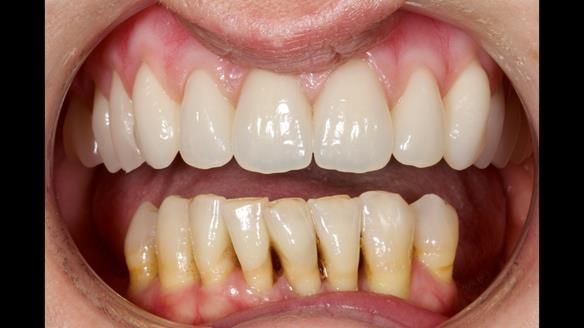

She had previously suffered from generalised periodontitis – stage IV, grade C, currently stable, with reduced attachment across the upper arch.

By the time she came to me, her periodontal condition was stable — but the aesthetics in the upper jaw were very poor.

We provided her with an immediate upper denture (Mk 1), followed by a definitive metal-based upper denture (Mk 2). A lower removable partial denture was discussed, to be made only if needed once the upper treatment was complete. However, at review, this wasn’t necessary — Adnana had excellent neuromuscular control and function, even with a shortened dental arch (SDA).

Rowan, Sam Hesketh and Chris Hesketh provided the stunning technical work. I am very lucky to have them.

- Immediate denture (Mk 1) fitted the same day the teeth came out

- Definitive denture (Mk 2), metal-based and custom-designed for her face

- A restored smile, restored lip support, and a patient who owned the journey